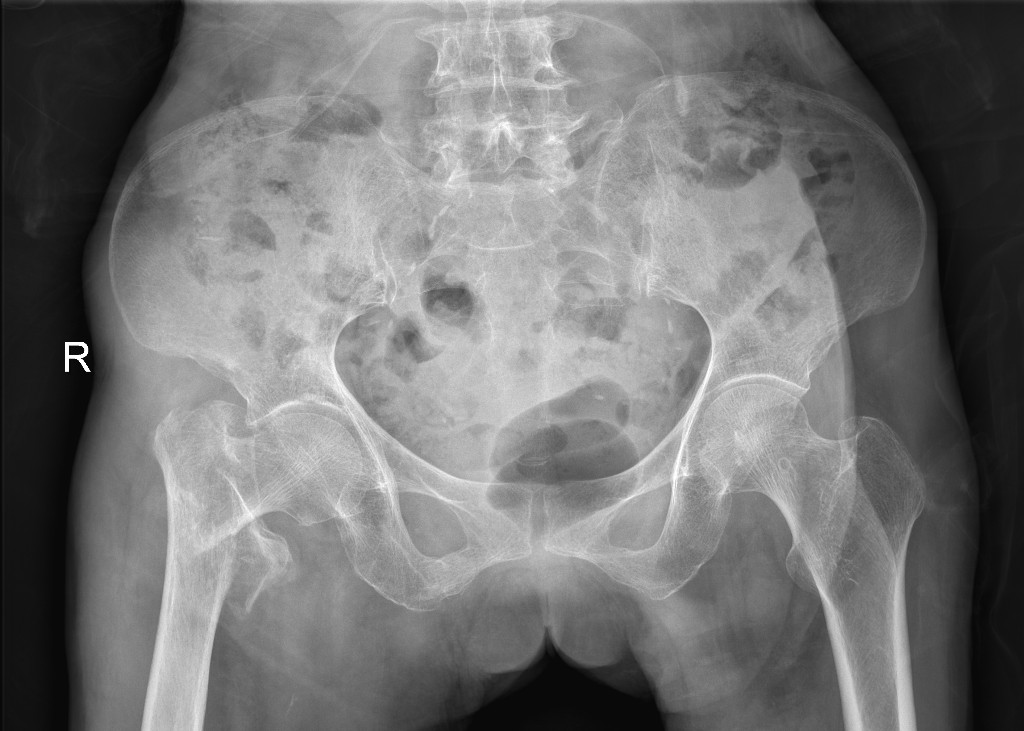

手术前X光片显示情况

来自巴马县的林阿婆今年已有83岁高龄。林阿婆一个月前在家中不慎跌倒,出现右髋部疼痛,不能站立行走。这突如其来的情况令家人焦急万分,于是急忙将老人送到我院急诊科就诊,值班医师立刻为其进行检查。X光片显示:右股骨转子间骨折。因病情严重,医护人员马上将其送入脊柱关节骨病外科进行治疗。